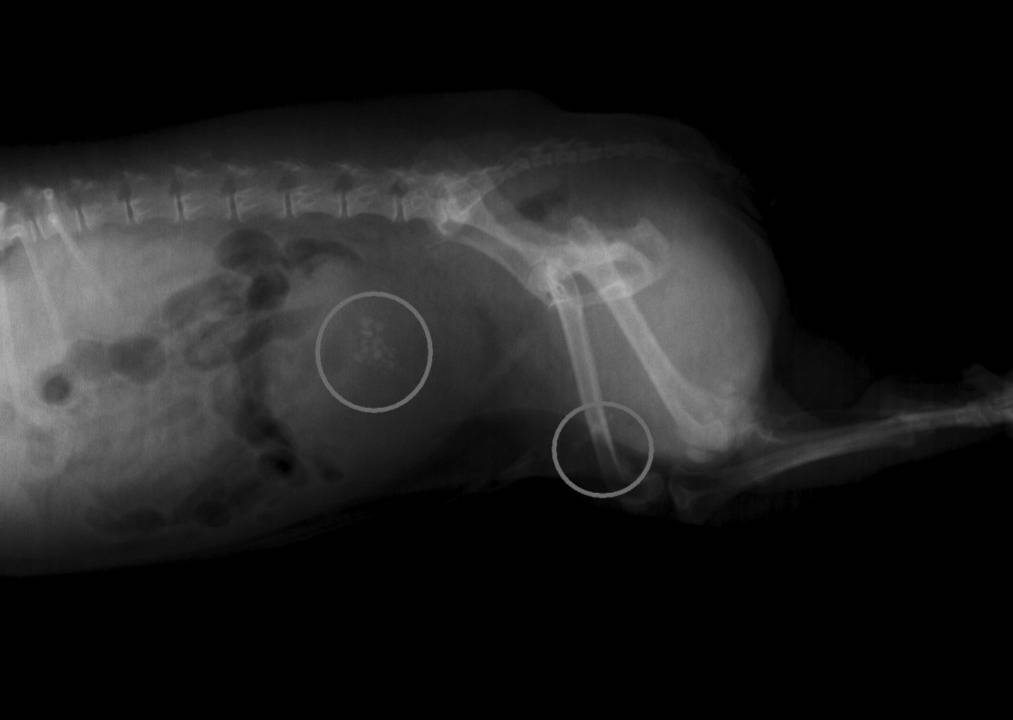

Cela peut être en effet une cystite qui se complique d'une obstruction des voies urinaires par des calculs le plus souvent, des bouchons de mucus ou des caillots sanguins parfois, et ce dans la partie la plus basse et la plus étroite des voie urinaires du mâle (à savoir l’urètre), au niveau du pénis. Une fois bouchée par ce sable de calculs, la vessie gonfle et devient douloureuse, on parle de « globe vésical » et l'animal rentre en insuffisance rénale très rapidement car des déchets azotés comme l'urée normalement éliminée dans les urines se concentrent dans le sang à des taux très élevés, et créent une défaillance rénale suivie d'un coma.

Il y a alors nécessité absolue de sonder la vessie pour lever l'obstruction, perfuser pour « nettoyer » le sang et analyser le type de calculs responsables pour donner ensuite le régime alimentaire adapté et éviter ainsi de rapides récidives.

Parfois des calculs volumineux sont déjà présents dans la vessie, nécessitant aussi une cystotomie, chirurgie qui consiste a aller chercher ces derniers directement sur place.